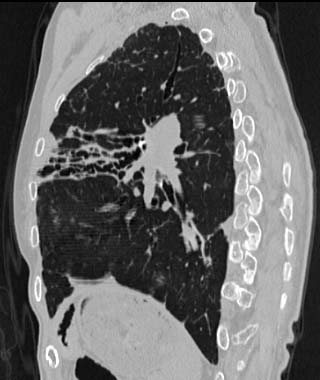

MPR

Data acquired & processed by R. Kato M.D.